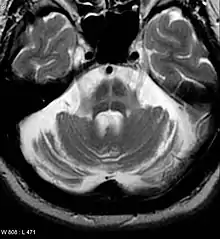

Computed tomography (CT) scans of people with PD usually appear normal.[109] Magnetic resonance imaging has become more accurate in diagnosis of the disease over time, specifically through iron-sensitive T2* and susceptibility weighted imaging sequences at a magnetic field strength of at least 3T, both of which can demonstrate absence of the characteristic 'swallow tail' imaging pattern in the dorsolateral substantia nigra.[110] In a meta-analysis, absence of this pattern was highly sensitive and specific for the disease.[111] A meta-analysis found that neuromelanin-MRI can discriminate individuals with Parkinson's from healthy subjects.[112] Diffusion MRI has shown potential in distinguishing between PD and Parkinson-plus syndromes, as well as between PD motor subtypes,[113] though its diagnostic value is still under investigation.[109] CT and MRI are used to rule out other diseases that can be secondary causes of parkinsonism, most commonly encephalitis and chronic ischemic insults, as well as less-frequent entities such as basal ganglia tumors and hydrocephalus.[109]